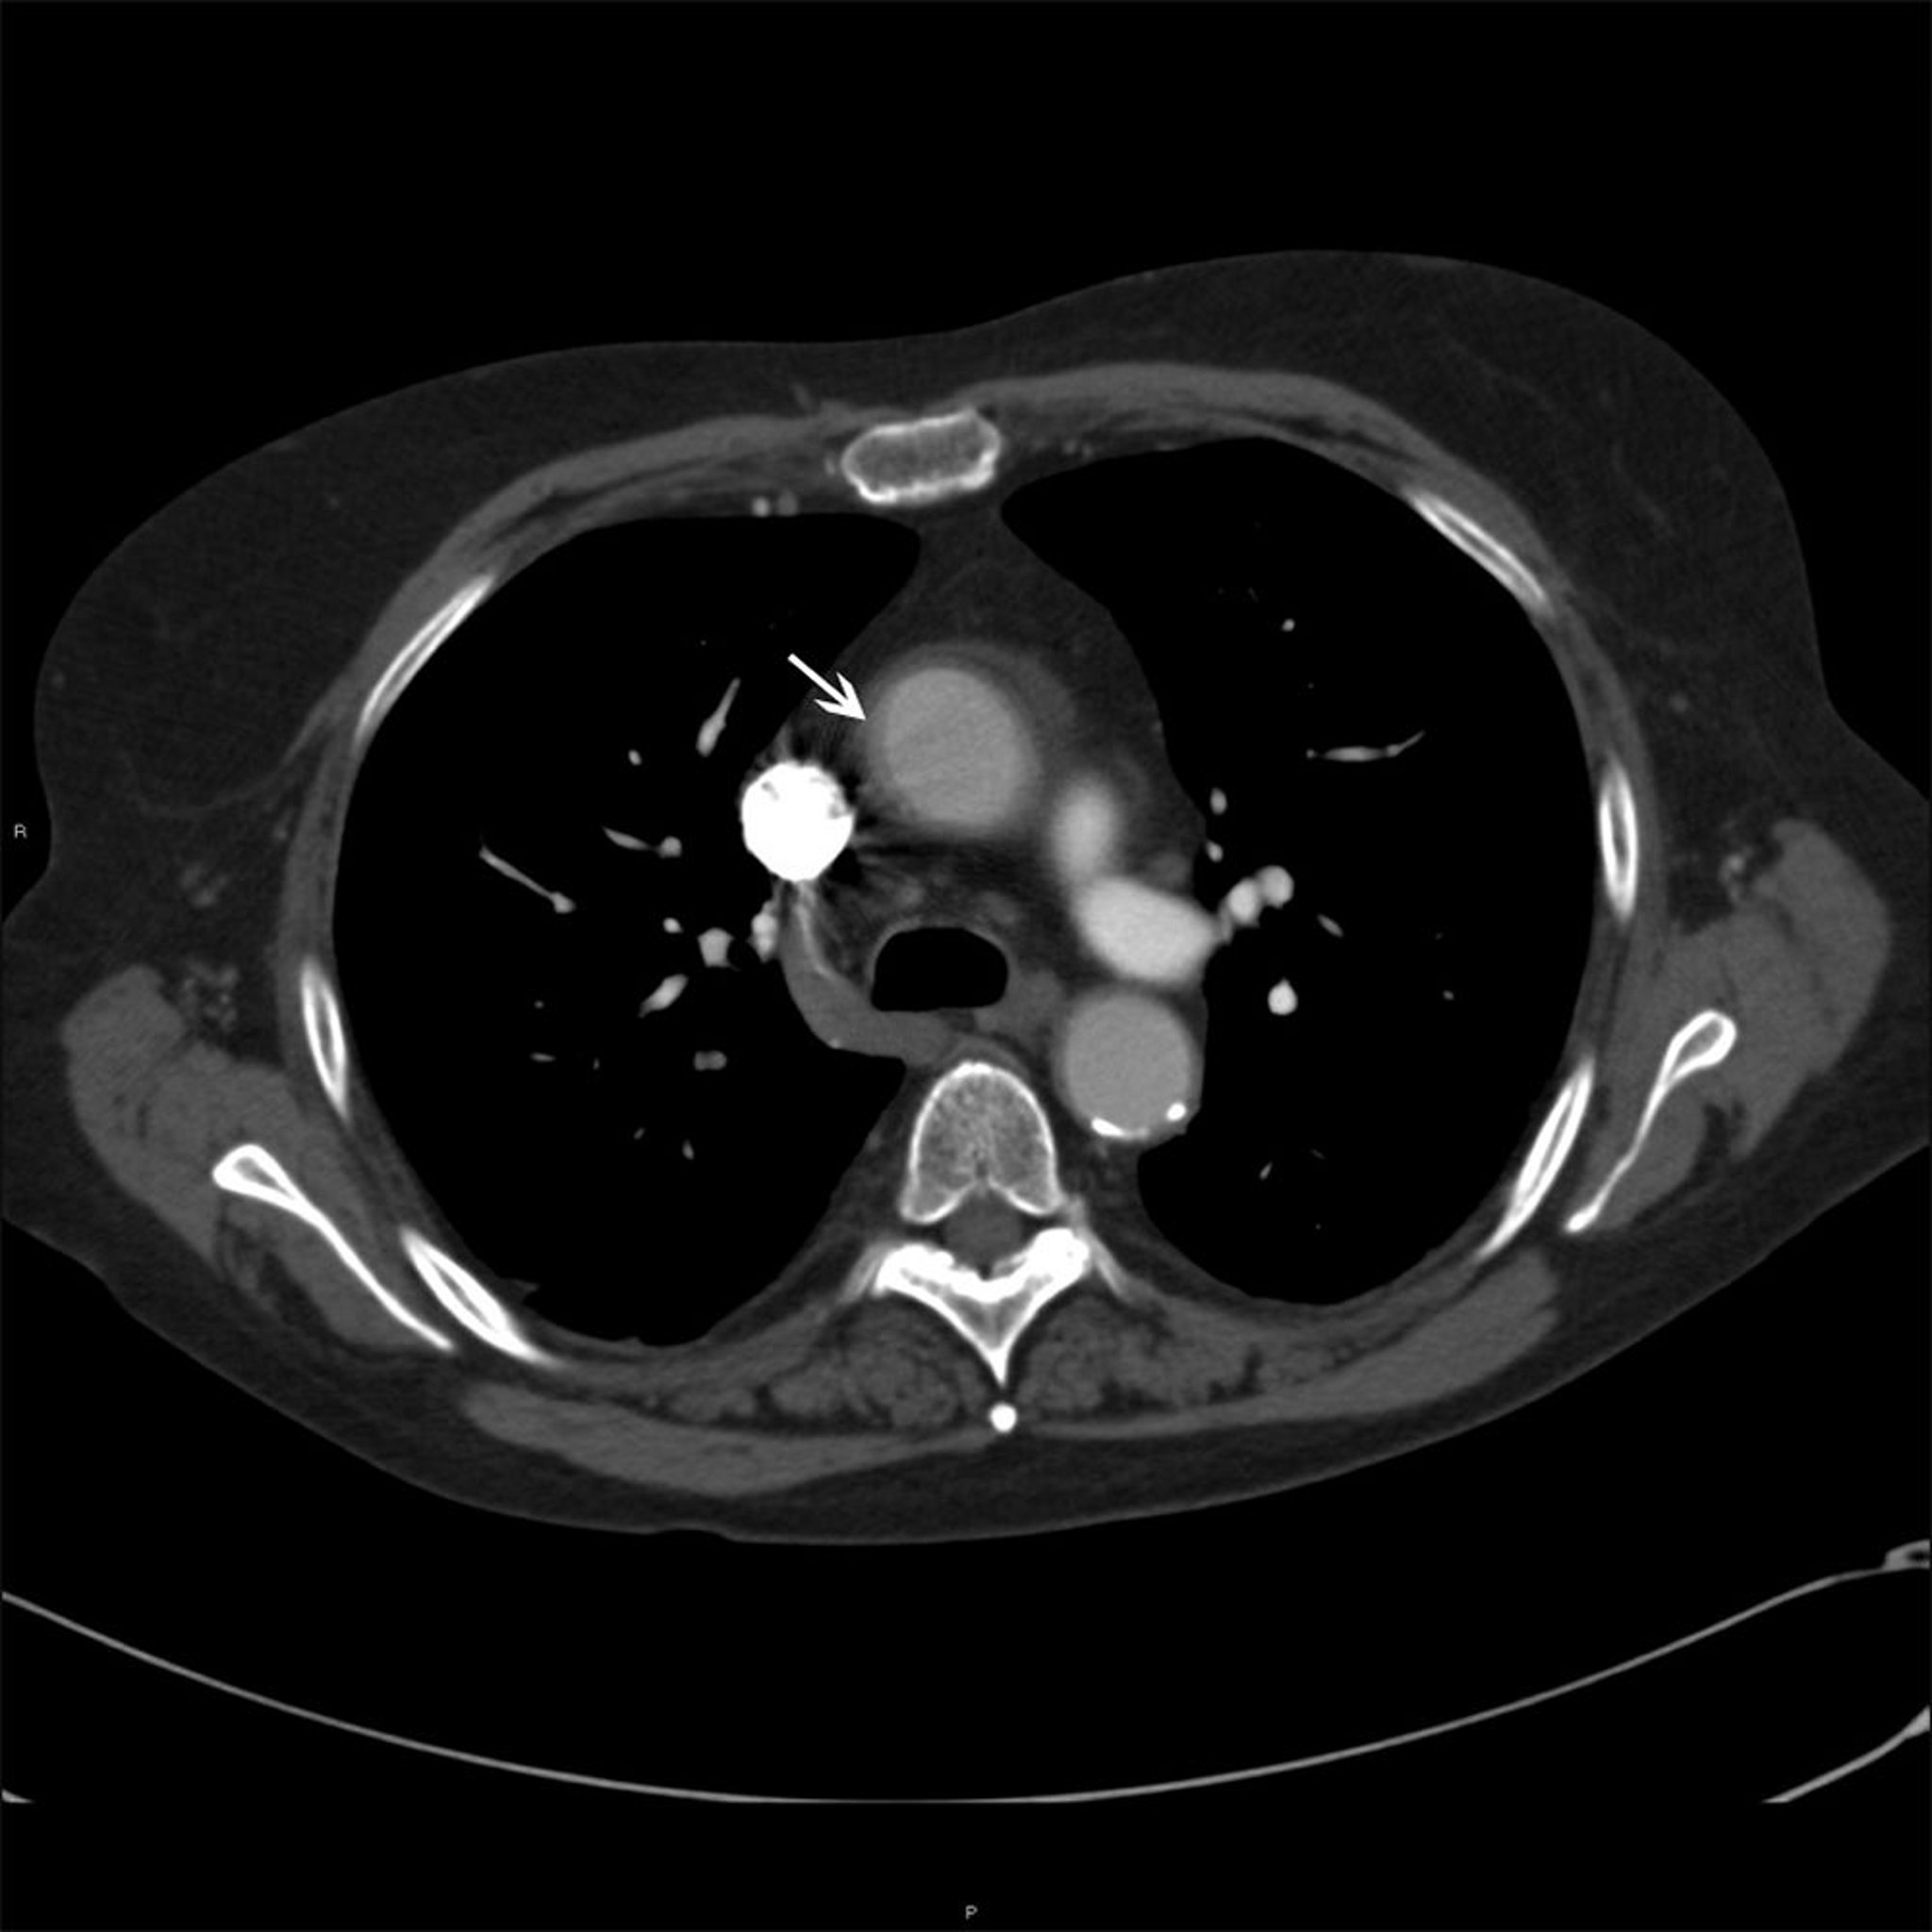

Ascending Aorta in Patient with Takayasu Arteritis

This photo shows mural thickening (white arrow) of the ascending aorta in a patient with Takayasu arteritis.